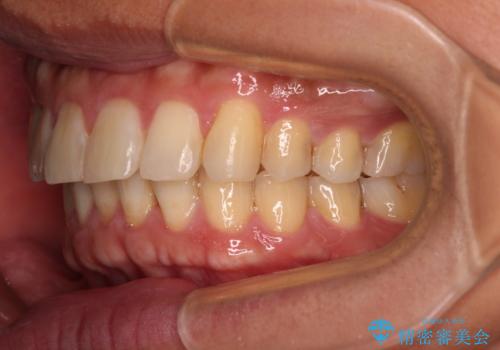

遠方からの通院 インビザライン矯正治療

- 20代男性

- インビザライン

- 4年8ヶ月

- 前歯のデコボコを気にして来院された患者様です。